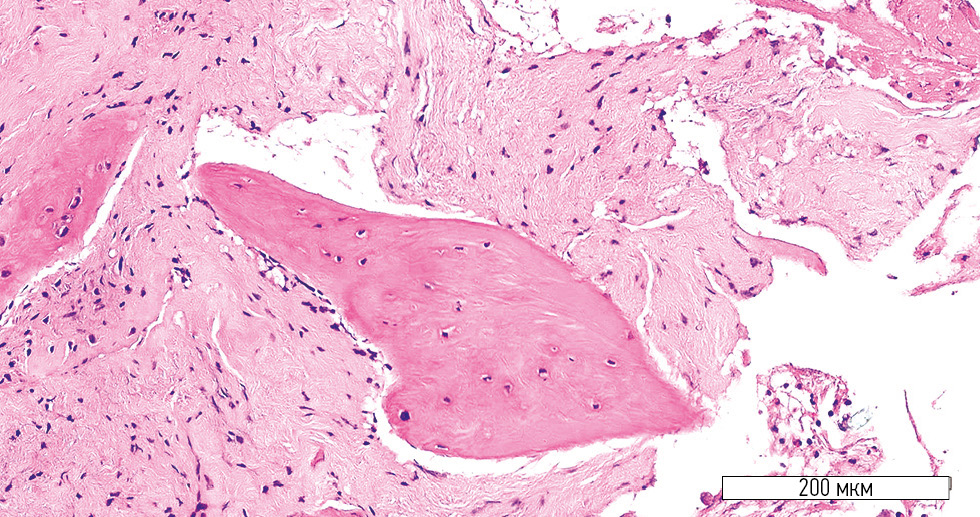

Microscopic evaluation after 4 months revealed substantial differences in the histological architecture of the regenerated bone between the treatment and control groups. In the treatment group, a well-developed stromal component and newly formed bone trabeculae were observed (Fig. 1). The stromal component consisted of densely packed mesenchymal cells with a minimal number of blood vessels per mm2 (Fig. 2). Areas of osteogenesis contained active osteoblasts, and the newly formed bone lamellae showed multiple lacunae, some with osteocytes and isolated osteoblasts (Fig. 3).

Fig. 3. Bone lamella containing osteocytes and isolated osteoblasts (treatment group). Hematoxylin-eosin stain; original magnification ×400.

Closer examination of the bone lamellae revealed areas of non-uniform osteogenesis (Fig. 4). Maximum bone density was observed at the periphery of the trabeculae, whereas the central zones showed regions with immature osteons.

Fig. 4. Bone lamella with heterogeneous structure (treatment group). Hematoxylin-eosin stain; original magnification ×400.